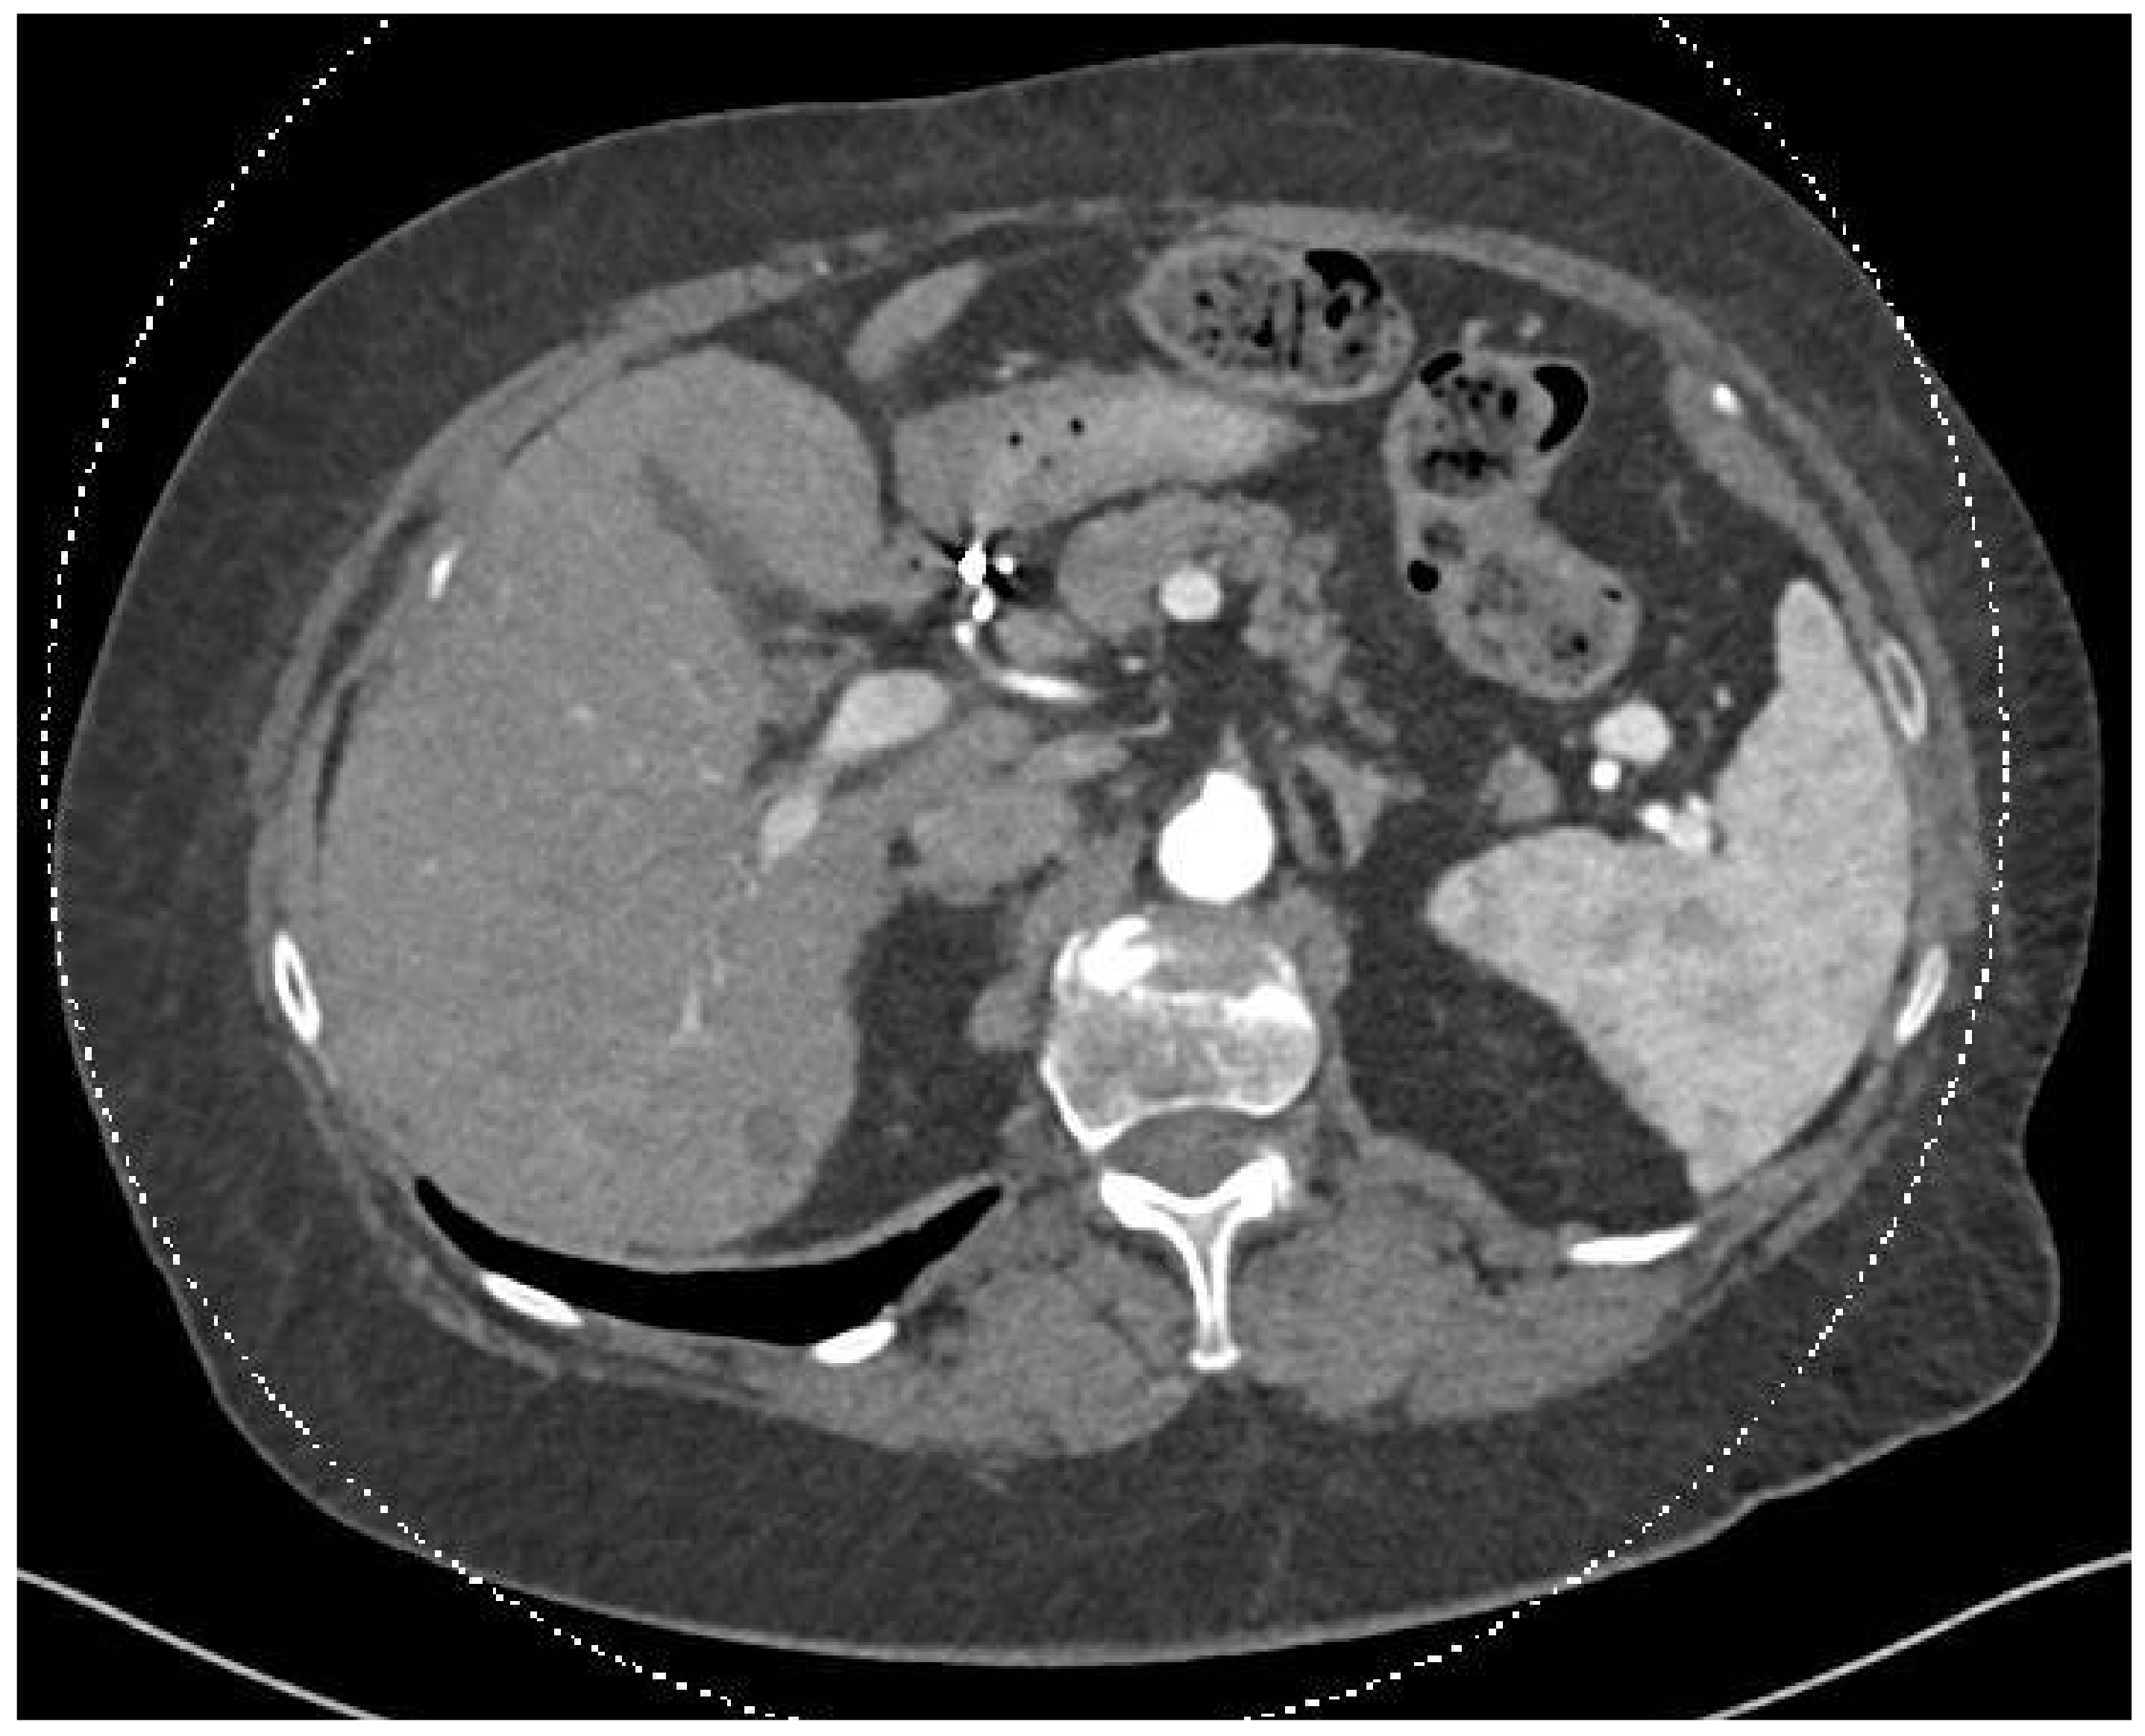

In December 2023, a full-body CT scan revealed that two known liver metastases had grown, and a new lesion had appeared near the inferior vena cava (IVC) in the liver. A multi-phase liver CT protocol performed later in December identified five lesions in the right liver lobe and at least one lesion in the left lobe (Figure 1). After consultation with an interventional radiologist, it was determined that the disease spread pattern was unsuitable for chemoembolization. Still, it was appropriate for selective internal radiation therapy (SIRT) using Yttrium-90. In February 2024, approximately one week before SIRT treatment, the patient underwent preparatory hepatic catheterization and selective simulation using Tc-99mma, demonstrating the feeding arteries to the liver tumors, and a low lung shunt fraction of 9% was calculated. During this preparatory hepatic catheterization simulation, the arteries feeding the tumors were mapped, allowing optimal catheter location placement (Figure 2). On 8 February 2024, the SIRT procedure was conducted under general anesthesia due to the patient’s back pain and inability to lie flat; a puncture was performed under local anesthesia, with fluoroscopy and ultrasound guidance, in the right common femoral artery. Catheterization of the superior mesenteric artery (SMA) was performed, and pressure injection showed no vessels from the SMA supplying the tumor. Subsequently, catheterization of the celiac artery was performed, with automatic injection showing celiac artery anatomy and pathological tumor enhancement in both liver lobes, particularly in the right lobe. A branch from the common hepatic artery was identified, supplying part of the right liver lobe, including at least two tumors. An accessory branch to the left lobe was observed through the left gastric artery, though it did not supply the liver tumors. Three doses of technetium were injected selectively into the right hepatic artery distal to the cystic artery, the left hepatic artery and a branch supplying part of the tumors in the right lobe, which originates from the proximal common hepatic artery. Due to the proximity of the origin of the right gastric artery, embolization with 2 mm coils was performed. At the end of the scan, the patient was transferred to the Nuclear Medicine Department, which showed a minimal lung shunt (9%) with no evidence of gastrointestinal shunt. The patient was then returned to the angiography suite for the second phase of the procedure. Selective catheterization of the three arteries was repeated, and technetium was injected with a total calculated dose of 1.4 GBq (0.4 to the left lobe, 0.4 to the systolic artery in the right lobe, and 0.5 to the right hepatic artery distal to the cystic artery). SIRT treatment was performed successfully with no apparent complications, and the patient was discharged home the next day.

Figure 1.

This abdominal and pelvic CT with contrast, performed on 25 December 2023, was compared to the previous abdominal CT from 15 August 2023 and the chest CT from 9 December 2021. The liver demonstrated two hypervascular lesions consistent with SFT: one lesion in segment 8 measuring 0.9 cm, previously 0.6 cm, and another lesion in segment 6 measuring 1.5 cm, previously 1.3 cm.